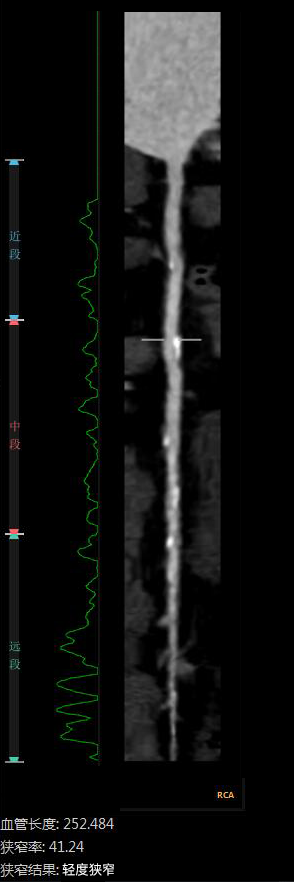

“CTA冠脉全自动诊断”

Automatic Coronary Diagnosis

②全自动量化测量

云端AI的CTA冠状动脉全自动诊断

重构了CTA冠脉检查的极简流程

数十倍地提升了工作效率

诊断质量得到AI赋能

变得更加稳定、优质